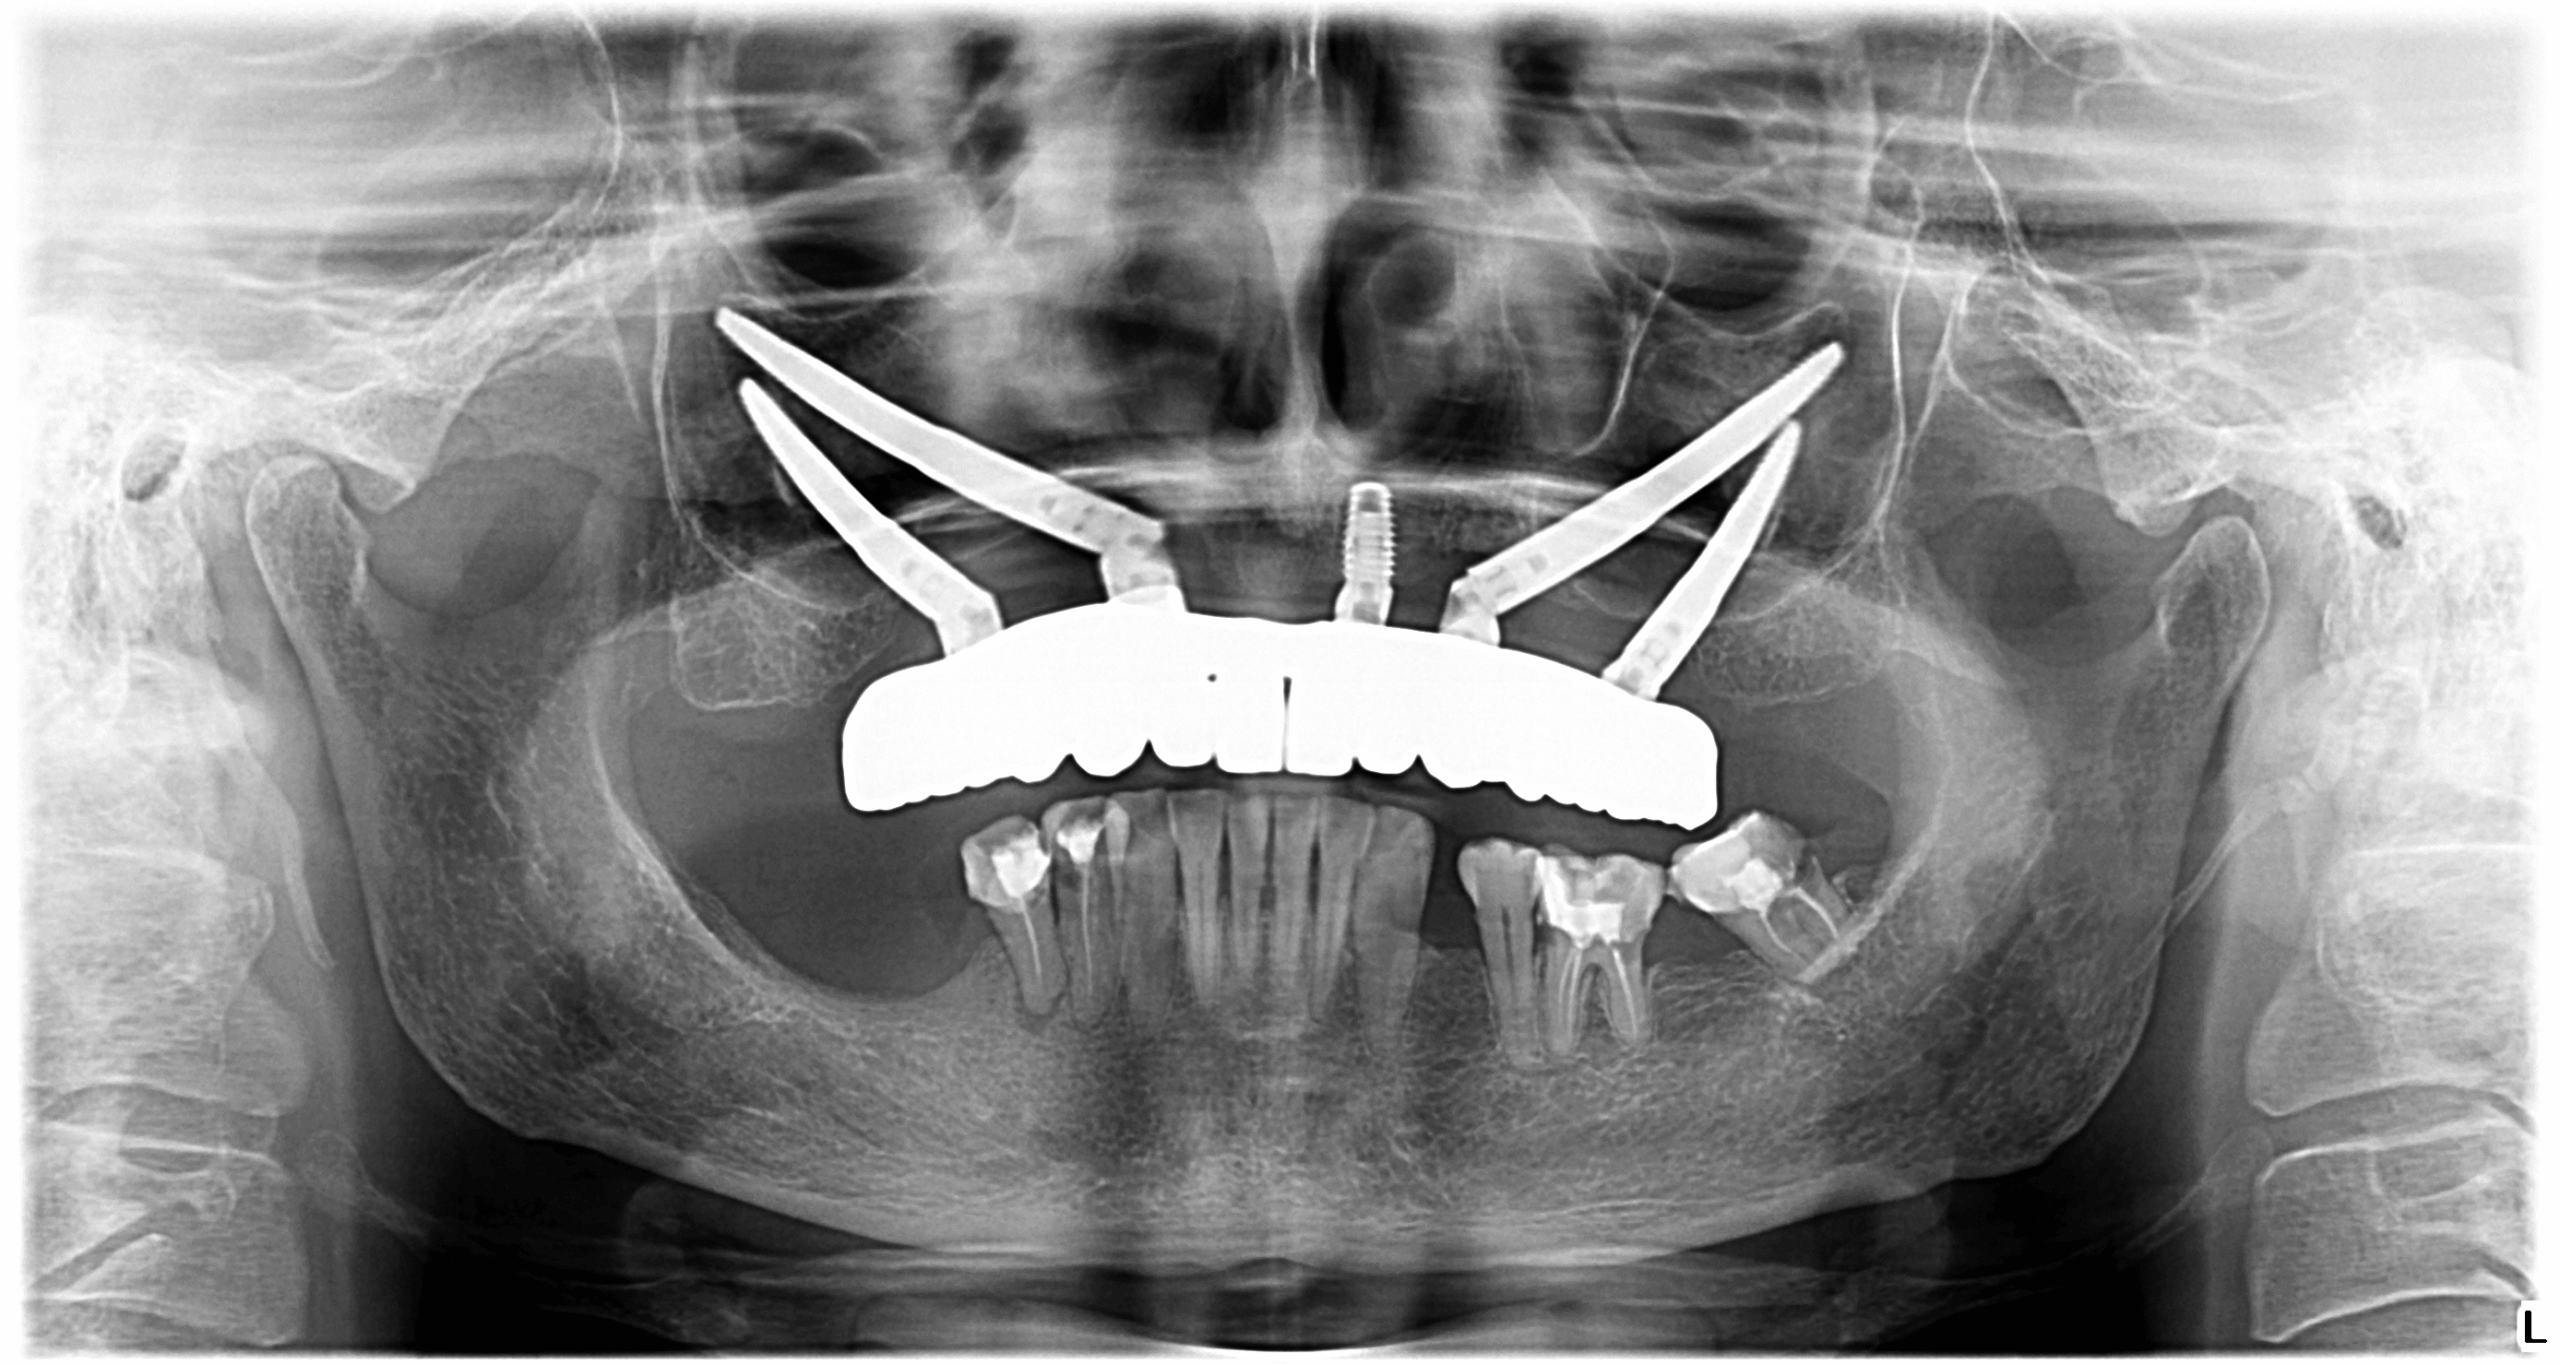

Dr Cazacu a sesizat cu ajutorul unei radiografii și a unui Computer Tomograf că pacientei nu i se potrivesc implanturile convenționale din cauza lipsei sale de os.

Pentru a putea susține o dantură fixă, doamna D. a avut nevoie de implanturi zigomatice, care inserate în puncte cheie au reușit să susțină o lucrare provizorie timp de 4-6 luni, iar acum o lucrare definitivă superbă pe care Doamna D. o poartă cu mare bucurie.